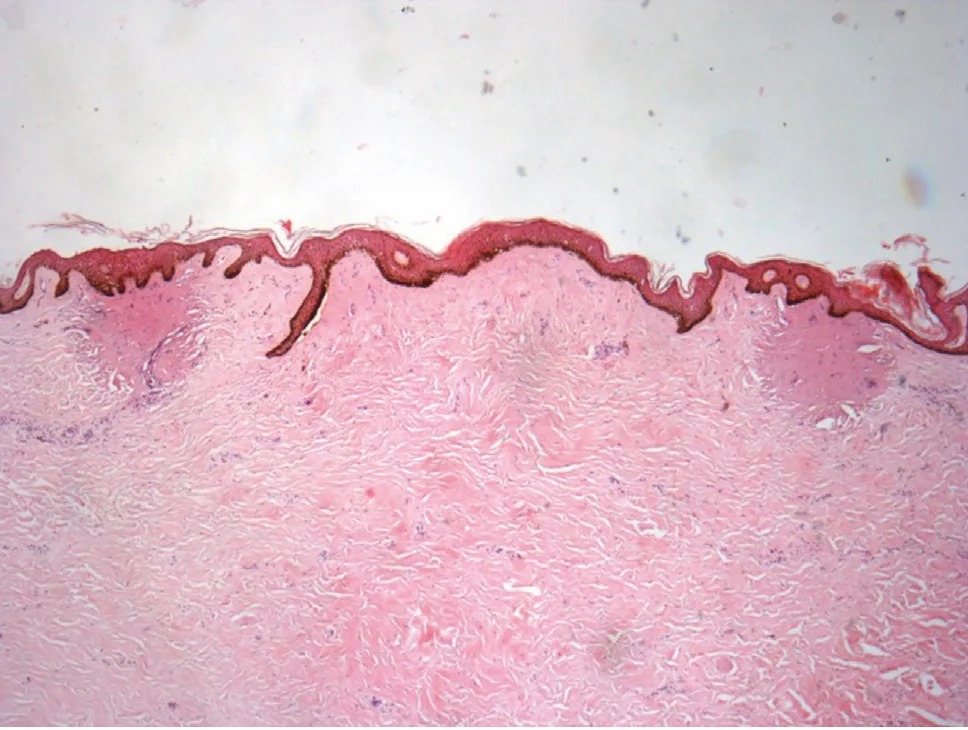

Histological evaluation of the skin demonstrated the differ-ent impacts obtained with the HE applicator using low or high parameters. Impact zones with unaffected intact areas in between were shown; about 5 impacts could be seen at ×40 magnification on the histological slides (skin biopsy was 11 mm in length). A section of a histological slide with 2 impact zones of treatment with high HE parameters is shown in figure 1. Affected epidermis and areas of con-densed dermal collagen are visible directly under the zones of impact.

Figure 1. Histology analysis of UV aged skin at D0 after expo-sure to high HE parameters (H&E stain, x40). 2 areas of impact are present with unaffected zone in between.